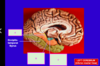

What type of brain herniations are A & B? [2]

A: Downward cerebellar (Tonsillar)

B: Upward cerebellar (transtentorial)

State what type of herniation A-D are [4]

A: **Cingulate** (Subfalcine) B: **Central** (**transtentorial**) C: **Uncal** D: Downward cerebellar (**Tonsillar**)